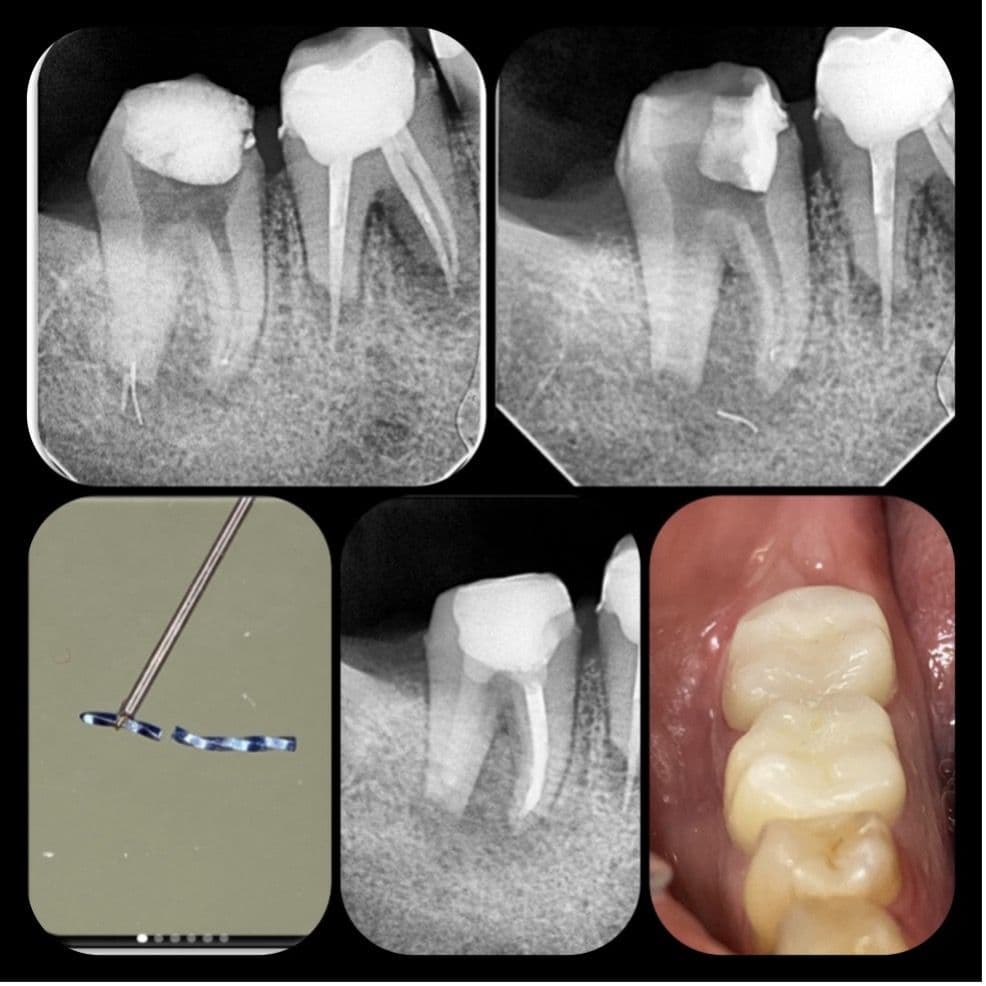

29 yaşındaki sağlıklı erkek hasta kök kanalındaki kırık eğe nedeni ile kliniğimize başvurdu. Yapılan radyografik muayenede distal kanalda apikalden taşkın guta ve kırık alet olduğu tespit edildi (RESİM 1).

RESİM 1: Apikalden taşkın eğe ve guta

Rubberdam izolasyonu sonrası tedaviye başlandı. Geçici dolgu kaldırıldığında distal kanalın apikalinde guta ve eğenin koronal bölümü izlendi (RESİM 2).

RESİM 2: Başlangıç fotoğrafı apikalde eğe ve guta

Kırık eğenin etrafından ultrasonik uç ile preparasyon yapılmaya çalışıldı ancak eğenin apikalde duvarla teması olmadığı ve tamamen granülasyon dokusu içerisinde olduğu anlaşıldı (RESİM 3).

Resim 3: Kırık eğenin granülasyon dokusu içerinde kayboluşu

Daha sonra kontrol röntgeni alındı ve eğenin konumu tespit edildi (RESİM 4).

RESİM 4: Kırık eğenin ve taşkın gutanın kök ucundan apikale ilerlediği tespit edildi

İlk seans kanallara kalsin yerleştirildi ve hastadan alınan tomografi incelendi. Yapılan 3 boyutlu değerlendirmede kök ucundaki lezyonlu alanın kemikle çevrili olduğu, alt kısımdaki mandibular kanalla ilişkisinin olmadığı tespit edildi ve tedaviye cerrahi olmadan ortograd yöntemle devam edilmesi kararı alındı (RESİM 5).

RESİM 5: Mandibular kanal ve taşkın eğenin olduğu bölge

Hastamız 2. Seansa geldiğinde kalsin temizlendi. Apikal bölgedeki taşkın guta 3 boyutlu aktivasyon eğeleri ile çıkarıldı ancak eğeye ulaşılamadı ve kontrol filmi alındı (RESİM 6).

RESİM 6: Kırık eğenin konumu kontrol edildi.

Alınan radyografta eğenin konumu teyit edildi ve bölgedeki granülasyon dokusu ophtalmic forseps ile eğe görünecek şekilde temizlendi. Kanalın apikali paper pointle kurutulduğunda eğenin koronal kısmı görüldü ve tel ilmik tekniği ile çıkarma işlemine geçildi. Tel ilmik ile eğe kökün dışında yakalandı ancak yakalama sonucu eğe kökün uzun aksı boyunca 90 derece açı yapacak şekilde takıldı (RESİM 7) ve koronale çekilemedi.

RESİM 7: Tel ilmikle yakalanan eğe görseldeki gibi köke dik konumda kaldı

Kuvvet uyguladığımızda eğenin bir kısmı kırılarak tel ilmik ile çıktı (RESİM 8). Kalan parça için RVG alındı ve parçanın lezyon içinde hareket ettiği ve distal kök ucundan uzaklaştığı anlaşıldı. Seans bitiminde kalsin yerleştirildi ve 3. randevu oluşturuldu.

RESİM 8: Kırılarak çıkan eğe parçası

3. seansa başlamadan aldığımız rvg de kırık eğenin mesial kök ucuna daha yakın olduğu tespit edildi. (RESİM 9). Mesial kanaldan serum irrigasyonu yaparak serumun distal kanaldan drene olması ve eğenin tekrar distal kökucuna taşınması planlandı. Plan işe yaradı kırık eğe distal apikal açıklıkta izlendi. (RESİM 10)

RESİM 9: Apikal bölgede hareket eden kırık eğe

RESİM 10: Distal apikalde kırık eğenin bir kısmı izlendi.

Ophtalmic forseps yardımı ile kırık parça yakalandı ve kök içine çekildi. Kök içine çekilen parça mikro opener yardımı ile koronale yükseltilerek kanal içerisinden çıkarıldı (RESİM 11).

RESİM 11: Apeks dışındaki parçanın çıkarılması

Kanala kalsin yerleştirildi (RESİM12). 4. seansta hastamızda herhangi bir semptom yoktu, distal kanal biodentin mesial kanallar guta ve Ahplus ile dolduruldu (RESİM13). Kanal tedavisi tamamlandıktan sonra dişin koronal restosrasyonu zırkonya kaplama ile gerçekleştirildi ve hastamız takibe alındı. (RESİM14)

RESİM 12: Kalsiyum hidroksit yerleştirilen kanallar

RESİM 13: Kanal tedavisi bitim röntgeni